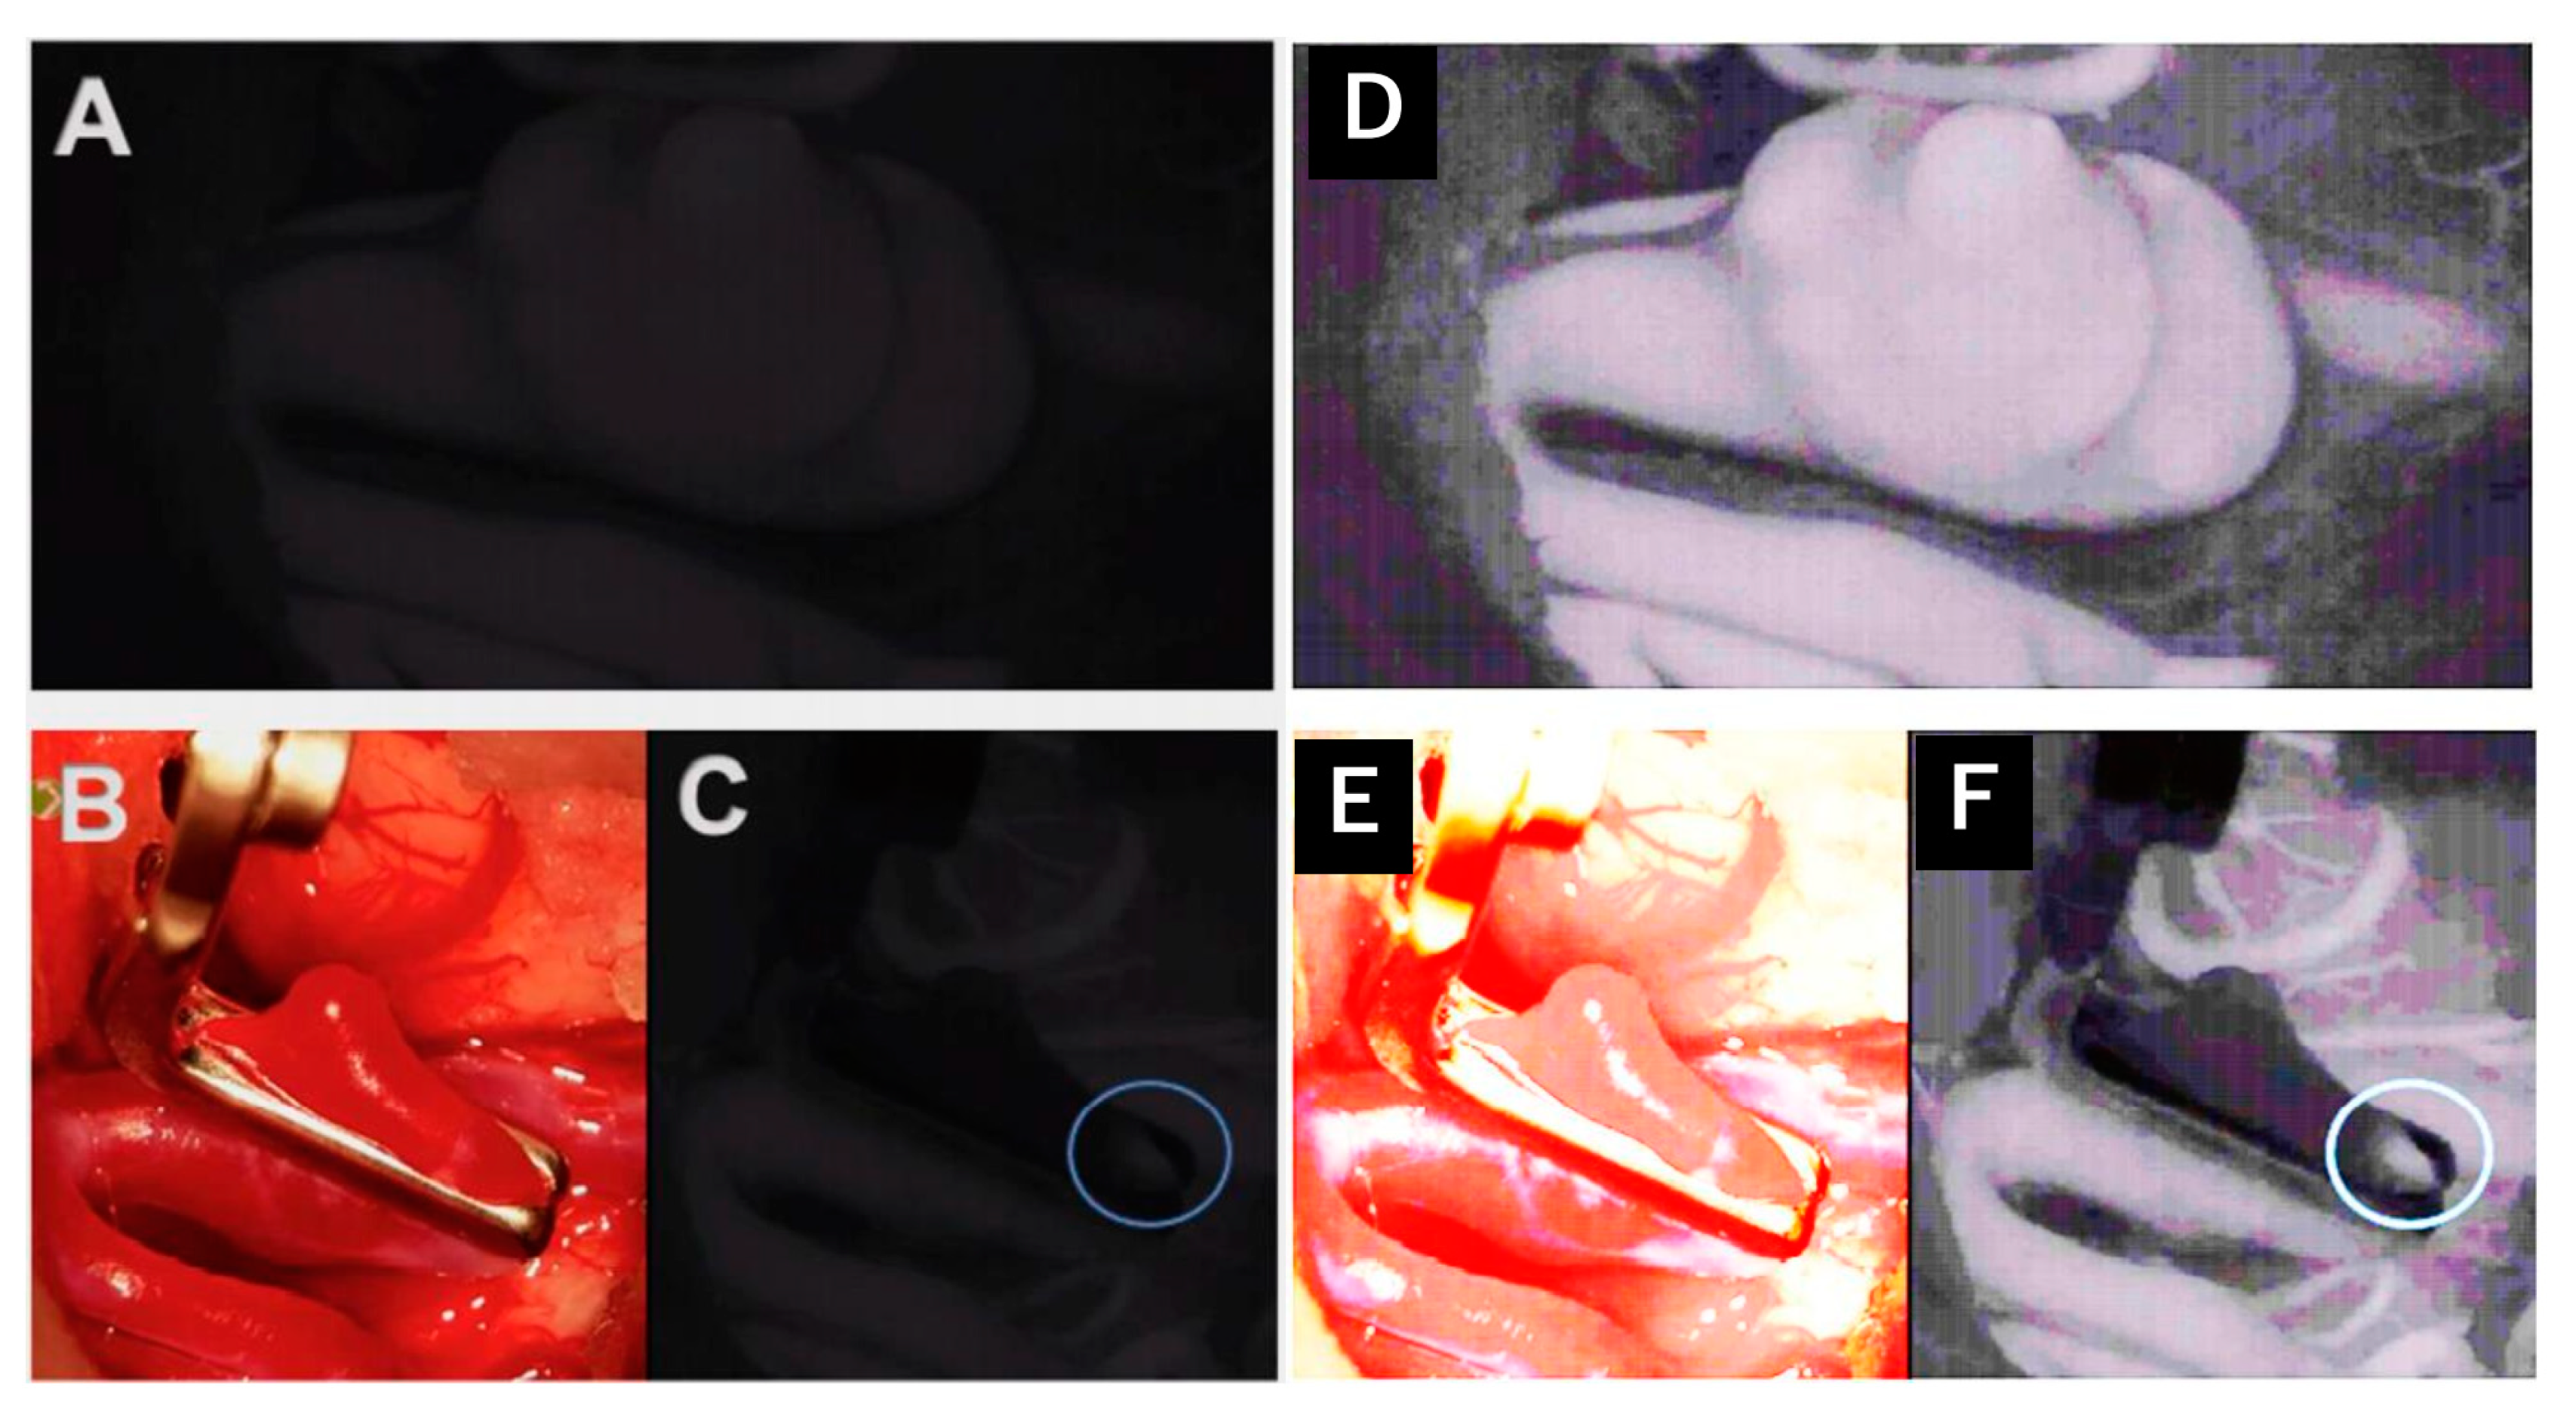

In our series, two cases of aneurysm clippings were rated as not (easy) suitable for the use of the Aeos, and the surgeon switched to the conventional microscope. These results differ from previous studies concerning the role of exoscopic surgery in the operative treatment of vascular cases [2,30], illustrating the need for larger studies that may elucidate predictive factors for the suitability of cases using exoscopic versus conventional microscopic techniques. In contrast, we felt safe to clip the aneurysm, but the different positioning was uncomfortable. Assuming that a pterional MCA and ICA-aneurysm clipping is one of the most standardized procedures in neurosurgery (instead of tumors, which were located differently), we have to focus on preparing the Sylvian fissure, which was uncomfortable due to the different positioning. Therefore, we would recommend having a conventional microscope next to an exoscope and training to use the exoscope. We used it in our fifth case and handled it well but not as fast as with conventional microscopes, which differs from the experience in other procedures. Figure 4A,C demonstrates the ICG mode of the Aeos system during the clipping procedure. For even better reference Figure 4D,F shows even enhanced contrast by image processing, which during the procedure is not necessary due to intraoperative high definition backlighted LED screen.

Figure 4. Intraoperative administration of indocyanine green during aneurysm clipping: Perception of indocyanine green during Aeos surgery in A and C. The unclipped aneurysm of the medial cerebral artery is dissected and visualized in (A). Visualization of the aneurysm under conventional light during surgery closed with a right-angled Sugita clip in (B). In (C) the light of the Aeos is on for post clipping control with indocyanine green. Rest perfusion in the clipped sack of the aneurysm at the right angle is highlighted with indocyanine green. Figure (DF) show even enhanced contrast by image processing, which however intraoperativly is not necessary due to high definition backlighted LED screen.